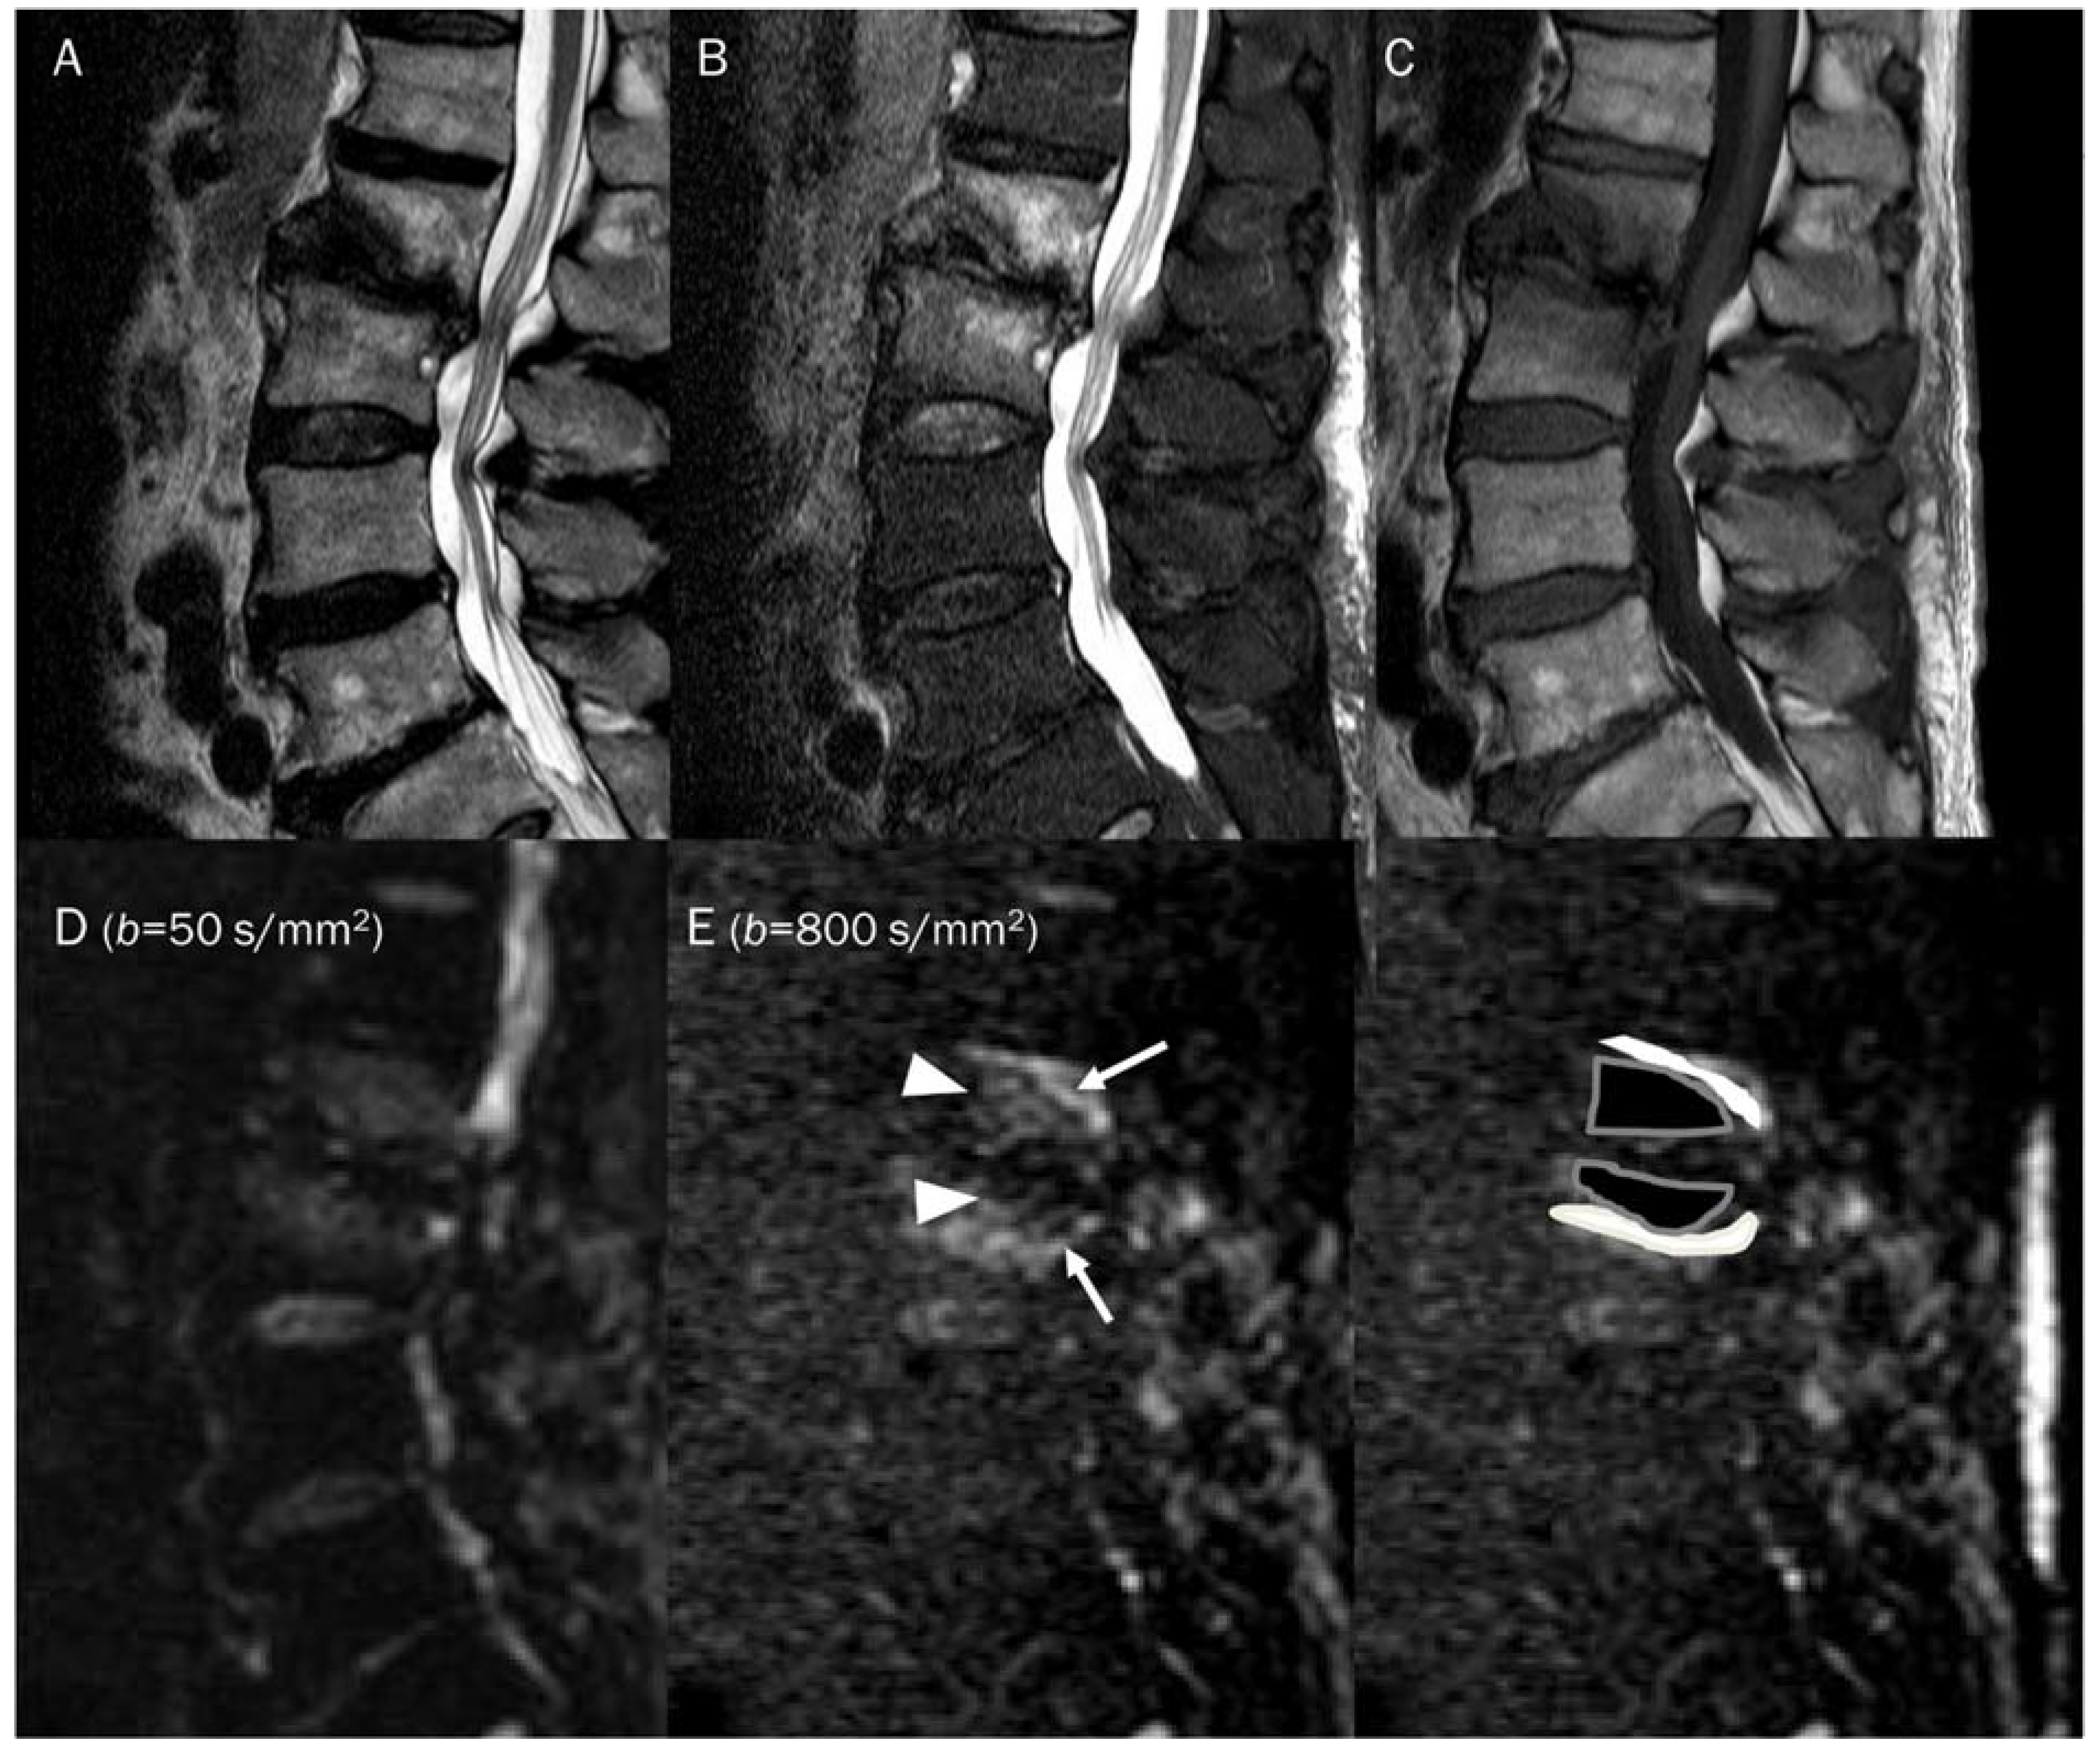

7.4. Vertebral Endplate Changes

- Modic, M.T.; Steinberg, P.M.; Ross, J.S.; Masaryk, T.J.; Carter, J.R. Degenerative disk disease: Assessment of changes in vertebral body marrow with MR imaging. Radiology 1988, 166, 193–199. [Google Scholar] [CrossRef]

- Braithwaite, I.; White, J.; Saifuddin, A.; Renton, P.; Taylor, B.A. Vertebral end-plate (Modic) changes on lumbar spine MRI: Correlation with pain reproduction at lumbar discography. Eur. Spine J. Off. Publ. Eur. Spine Soc. Eur. Spinal Deform. Soc. Eur. Sect. Cerv. Spine Res. Soc. 1998, 7, 363–368. [Google Scholar] [CrossRef]

- Oztekin, O.; Calli, C.; Kitis, O.; Adibelli, Z.H.; Eren, C.S.; Apaydin, M.; Zileli, M.; Yurtseven, T. Reliability of diffusion weighted MR imaging in differentiating degenerative and infectious end plate changes. Radiol. Oncol. 2010, 44, 97–102. [Google Scholar] [CrossRef]

- Patel, K.B.; Poplawski, M.M.; Pawha, P.S.; Naidich, T.P.; Tanenbaum, L.N. Diffusion-weighted MRI “claw sign” improves differentiation of infectious from degenerative modic type 1 signal changes of the spine. AJNR Am. J. Neuroradiol. 2014, 35, 1647–1652. [Google Scholar] [CrossRef]

| Modic type 1 vertebral endplate change | T2 black-out | Lipid laden cells |